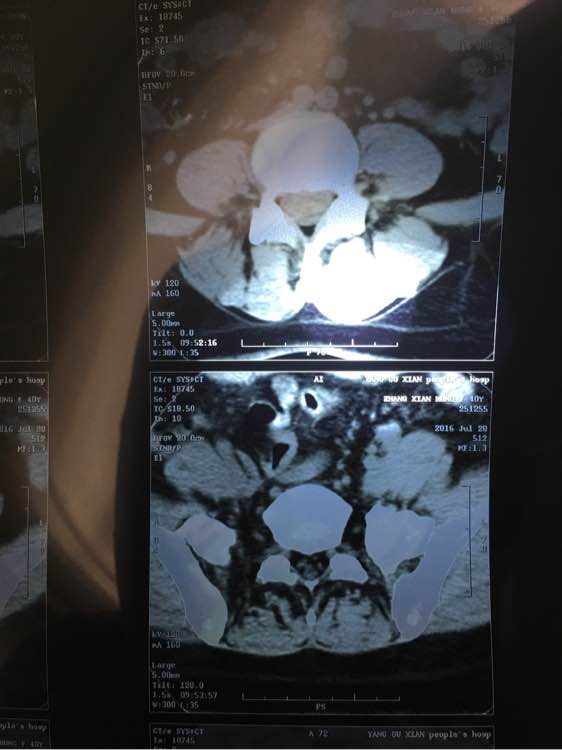

今天做了腰椎CT,却发现旁边有3个圆形黑点,特别明显,不知道是什么?内行的大神们给看下,拜托拜托了!